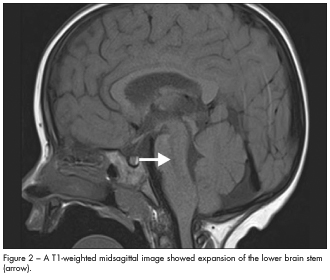

In this case, MRI scans of the brain revealed an infiltrative mass in the brain stem that involved the lower pons and medulla (Figures 1 and 2). This suggested a probable diagnosis of low-grade brain stem glioma. The child did not undergo brain biopsy for tissue diagnosis because of the critical location of the tumor. He was closely monitored by the neuro-oncology team. At follow-up 9 months later, an MRI scan showed the lesion to be stable; neurological findings were unchanged.